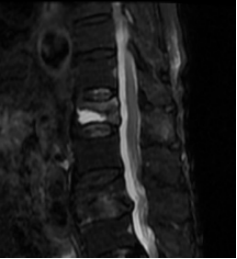

▲磁共振提示胸12骨折

同时,团队反复研究MRI图像和AI生成的三维椎体模型,精确测算出塌陷椎体所需“骨水泥”的理想体积——4.5ml。“这个数字绝非随意,注入过少无法有效支撑,注入过多则可能渗漏压迫神经或造成栓塞。”梁晓解释。